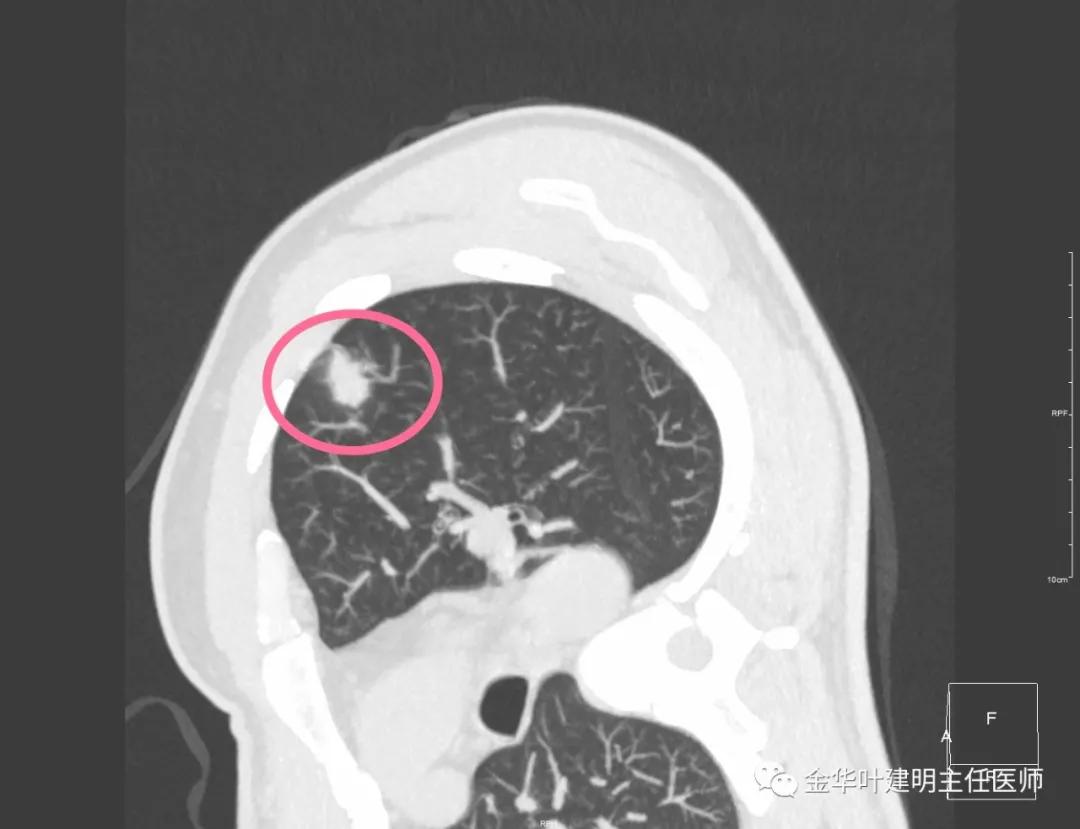

此层面红色箭头示有卫星灶,粉色箭头示主病灶

红色示卫星灶,粉色示病灶,绿色示边缘晕征